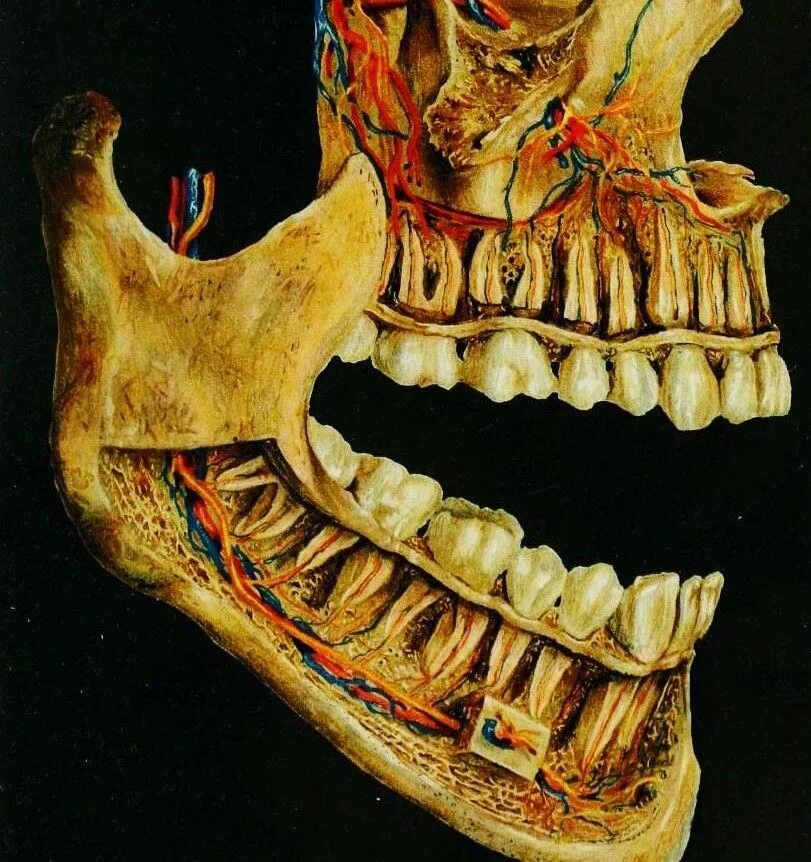

Снимок верхней и нижней челюсти